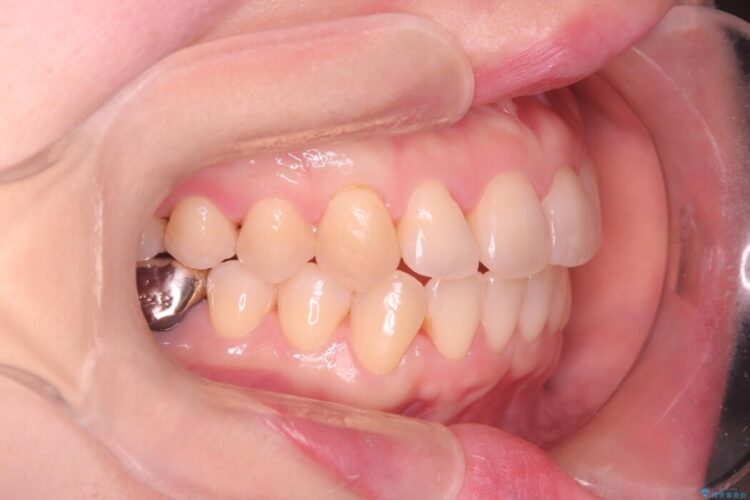

前歯が内側にねじれている状態を改善したいとの主訴で来院されました。

翼状捻転とは上顎前歯がまるで鳥の翼のように左右対称にねじれている状態をいいます。

本症例は正にその例です。

下顎にも叢生が見られたため上下の歯列をインビザラインにて整える計画を立てました。

ですが経過して確認した変化量から上顎のねじれが納得できる改善に至らないと判断しましたので途中からワイヤーを使用して矯正治療を行いました。

治療終了にあたり特に気にされていた前歯のねじれによってガタついていた歯列が改善されてご満足いただけました。